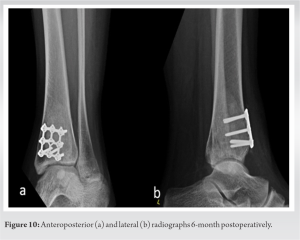

At 6-month follow-up, the patient was pain-free, walking full weight bearing with a below-knee boot. Radiographs show satisfactory bone growth at the level of the surgery (Fig. 10).